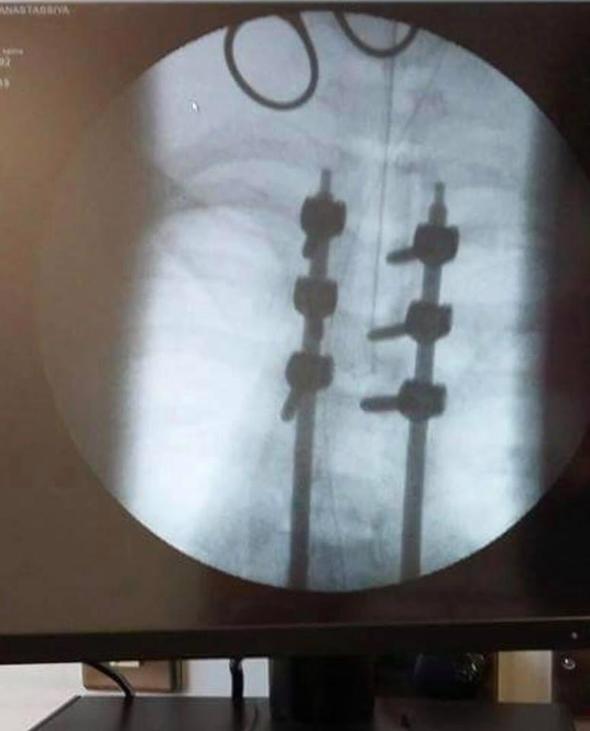

Anastassiya Kravtsova adlı genç kız 2015 Mart'ta İngiltere'de geçirdiği kaza sonrası hayatı adeta kabusa döndü.

Erkek arkadaşının sürdüğü araçta geçirdiği korkunç kazadan sonra felç kalan genç kadın ikinci darbeyi de erkek arkadaşından yedi.

Hastaneye kaldırılan kişiler, 16 yaşındaki Anastassiya Kravtsova ve 1 yıllık sevgilisi Beres Szabolcs'ti. Anastassiya, sevgilisi ile 15 yaşındayken tanışmıştı, Beres o zamanlar 24 yaşındaydı.